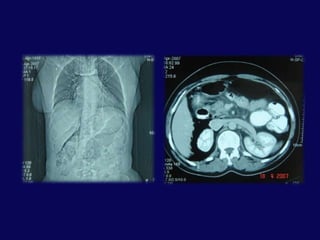

Akut BT bulguları• Direk bulgular– Pankreatik genişleme– Laserasyon– Heterojen kontrastlanma• Sekonder bulgular– Peripankreatik çizgilenme– Peripankreatik sıvı kolleksiyonu– Splenikvenve pankreas arasında sıvı kolleksiyonu– Kanama

BT: pankreas orta hatta laserasyon ve peripankreatik sıvı

SK 6,E